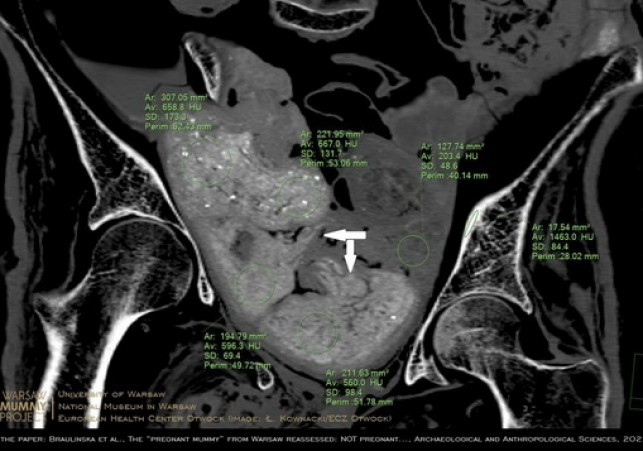

W lipcu 2022 ukazała się bogato ilustrowana publikacja w "Archeological and Anthropological Sciences" (DOI: 10.1007/s12520-022-01598-z), w której inny zespół badaczy z WMP dowodzi, że zmumifikowana kobieta z pewnością nie zawiera w sobie płodu. Świadczą o tym przede wszystkim obrazy precyzyjnie zrekonstruowanej zawartości miednicy oraz wyniki badań porównawczych starożytnych płodów egipskich.

Naukowcy ustalili, że w miednicy wcale nie ma płodu - jak sugerowali autorzy doniesienia z 2021 r. - ale cztery pakunki.

To właśnie trzy z czterech pakunków w miednicy poprzedni zespół zinterpretował jako płód. O tym, że kobieta nie była w ciąży, świadczą też ilościowe pomiary gęstości radiologicznych, a także wzajemne relacje geometryczne pakunków oraz porównawcza charakterystyka materiałów znajdujących się wewnątrz mumii - argumentują badacze w nowo opublikowanym artykule.

Autorzy nowego artykułu podkreślają, że wykorzystali te same dane uzyskane metodą tomografii komputerowej, co poprzedni zespół oraz m.in. to samo oprogramowanie.

"Wykazaliśmy w ten sposób, jak bardzo analizy efektów trójwymiarowych i ich interpretacja zależą od umiejętności użytkownika oprogramowania, który może osiągnąć doskonałe efekty wizualizacji również nie będąc radiologiem" - powiedział PAP dr Kownacki.